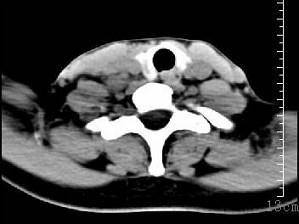

问题 女性35岁,发热、盗汗近3个月,颈部摸到多个结节,CT扫描如图所示,请选择最可能的诊断 ( )

选项 A、淋巴结核 B、淋巴瘤 C、结节病 D、淋巴转移癌 E、神经鞘瘤

答案 A